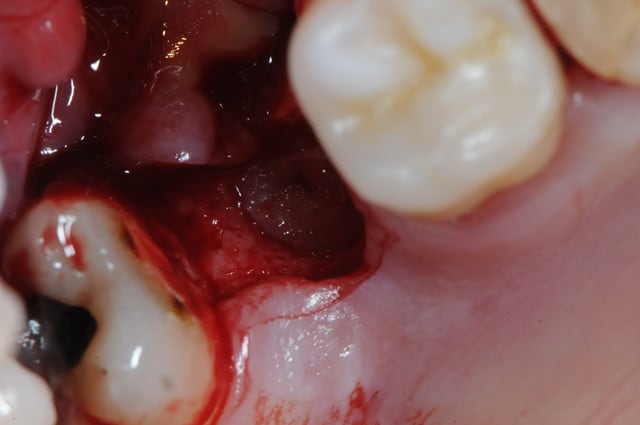

photo 1:

je cherche, je cherche, je soulève la membrane, et ..ohh! surprise!?

le dodo lé pas là !

mais ou est il ?

merde! ce con d'implant est parti faire un tout de poney sur sa selle turcique ou quoi ?? il est aller boire un coup avec les amygdales ?

bon, ben, si c'est pas resté sous le sinus, c'est que c'est dedans!

pas de pus, ni d'écoulement purulent pendant le soulèvement. comme il faut bien le trouver, je cherche sans ménager la membrane et ce qui devait se passer arriva; déchirure de la membrane.

pour une fois c'était presque voulu.

une fois percée, j'ai littéralement vidé le sinus du pus qu'il contenait avec l'aspiration.

2: comme il me fallait insérer la canule d'aspiration à travers l'opercule de la membrane pour vider le contenu sinusien, et comme l'aspiration venait me faire ch... à aspirer la membrane, j'ai décidé de la suturer sur le petit pont osseux pour la rendre plus stable.

après de longues recherches et avec de la chance je l'ai enfin sorti. toutes la salle s'est écriée " ça y est le voilà!"

j'ai alors dit au patient; " félicitation, c'est un garçon!"